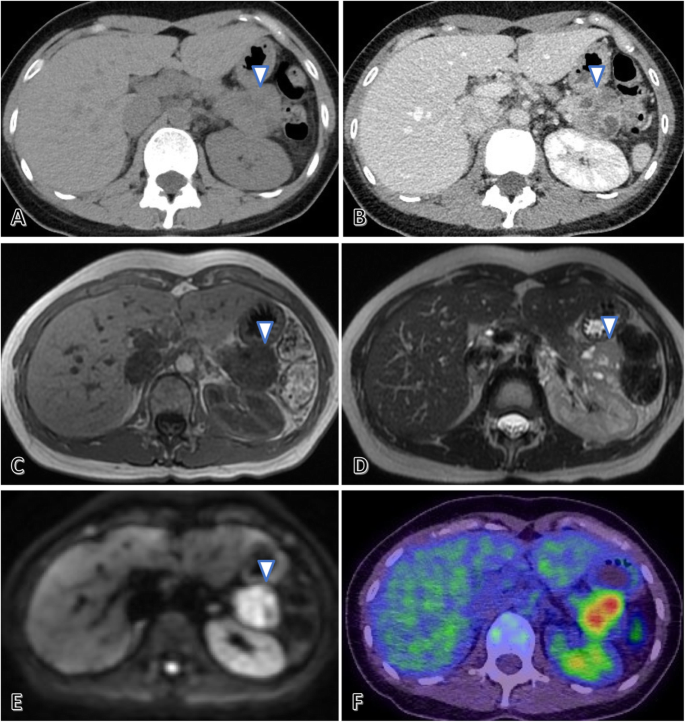

Contrast-enhanced thoracoabdominal CT revealed a large, 35-mm tumor in the pancreatic tail (Fig. 1a, b) showing heterogeneous contrast enhancement without calcification or bleeding. Lymphadenopathy and distant metastases were not observed.

Radiological findings of the pancreatic tail tumor. Non-contrast abdominal computed tomography (CT) reveals a large, 35-mm tumor in the pancreatic tail without calcification (arrow) (a). Contrast-enhanced CT shows that the tumor had heterogeneous contrast enhancement without bleeding (arrow) (b). Abdominal magnetic resonance imaging reveals that the pancreatic tail tumor (arrow) presented as a low signal area on the T1-weighted image (c), a slightly hyperintense tumor containing multiple cystic components on the T2-weighted image (d), and a high signal area on the diffusion-weighted image (e). Positron emission tomography CT indicates abnormal fluorine-18 fluorodeoxyglucose accumulation only in the pancreatic tail tumor (f)

Abdominal magnetic resonance imaging (Fig. 1c–e) revealed that the tumor in the pancreatic tail was similar to that in the primary left femoral lesion, showing a low signal on the T1-weighted image, a slightly hyperintense tumor containing multiple cystic components on the T2-weighted image, and a high signal on the diffusion-weighted image. The inside of the pancreatic tail tumor was heterogeneous and partly showed a water signal that was indicative of necrosis. 18F-fluorodeoxyglucose positron emission tomography CT revealed abnormal fluorodeoxyglucose accumulation only in the tumor of the pancreatic tail, with no other metastatic findings (Fig. 1f).